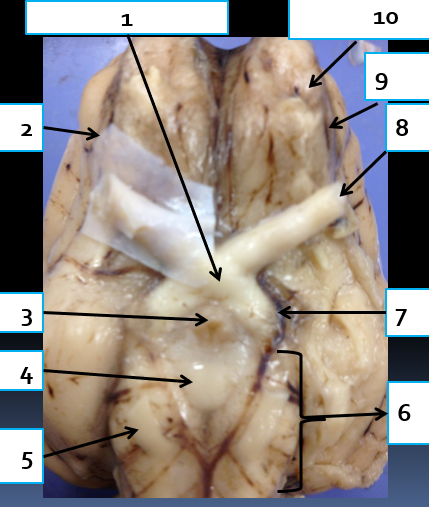

1

cerebral hemisphere, complex reasoning

2

olfactory bulb, houses synapses of olfactory nerve fibers, CN1

3

olfactory tract, carries impulses associated with sense of smell to the brain

4

dura mater, protects the brain

5

sulcus, increase brain surface area

6

gyrus, increase

7

arachnoid mater, protects brain by housing cushioning CSF